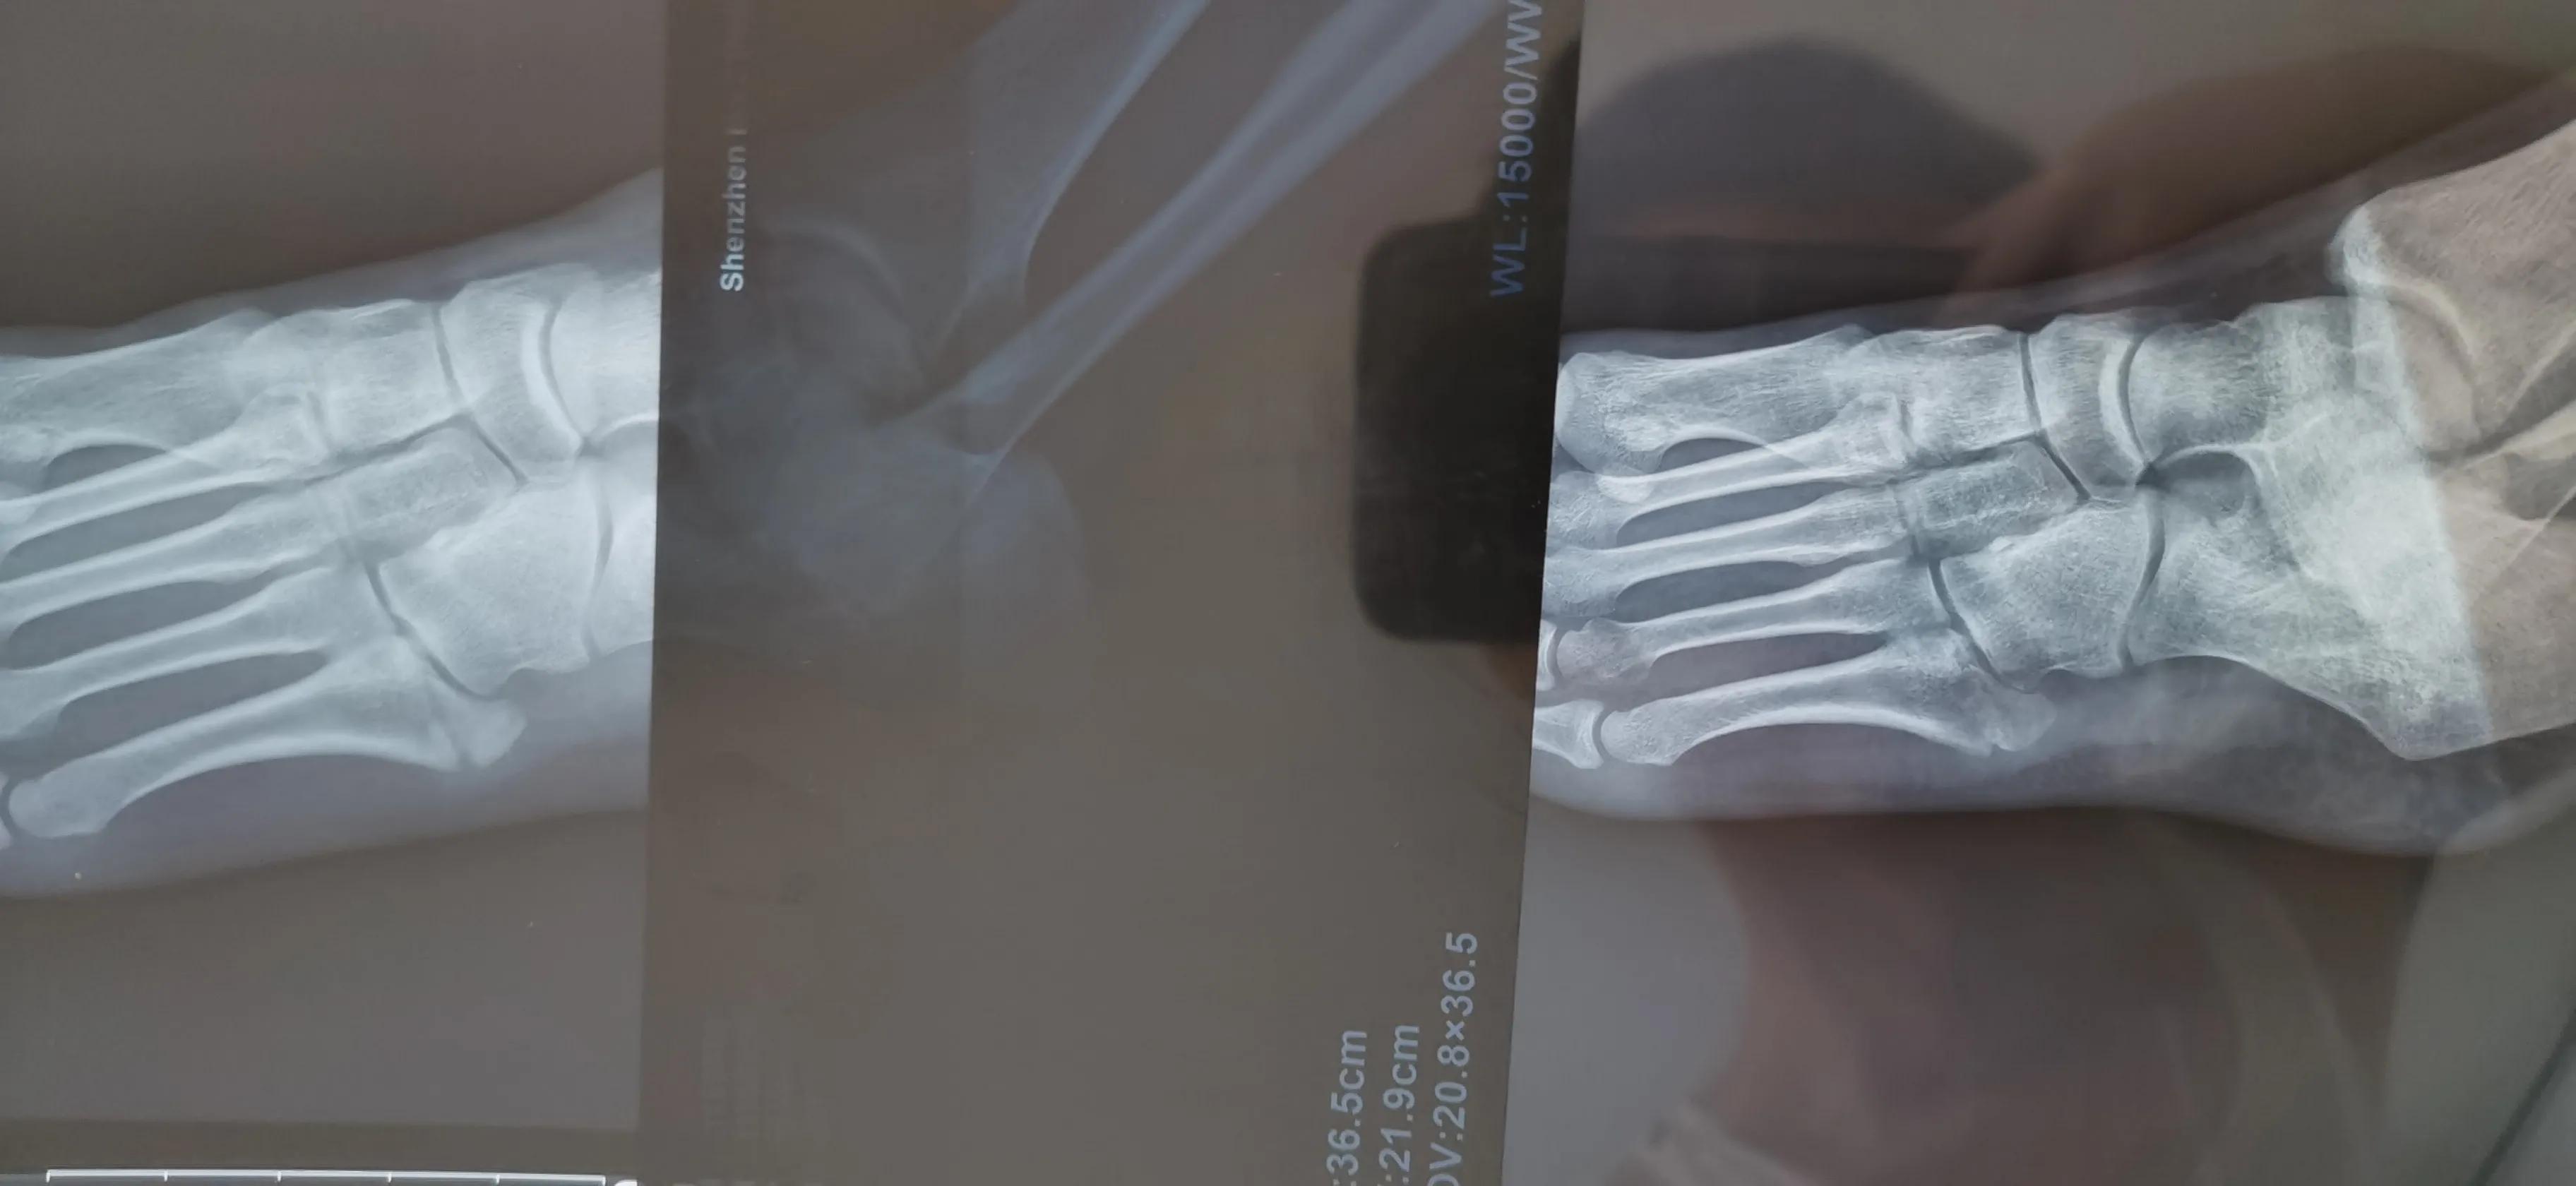

这是CT诊断书

7月底拍了一个CT,愈合不明显,原来第四跖骨也有骨裂,之前都没发现,所以一定要去好医院,好医院器材好,医生经验丰富诊断准确水平高,态度也很有耐心很负责

对比6月和8月